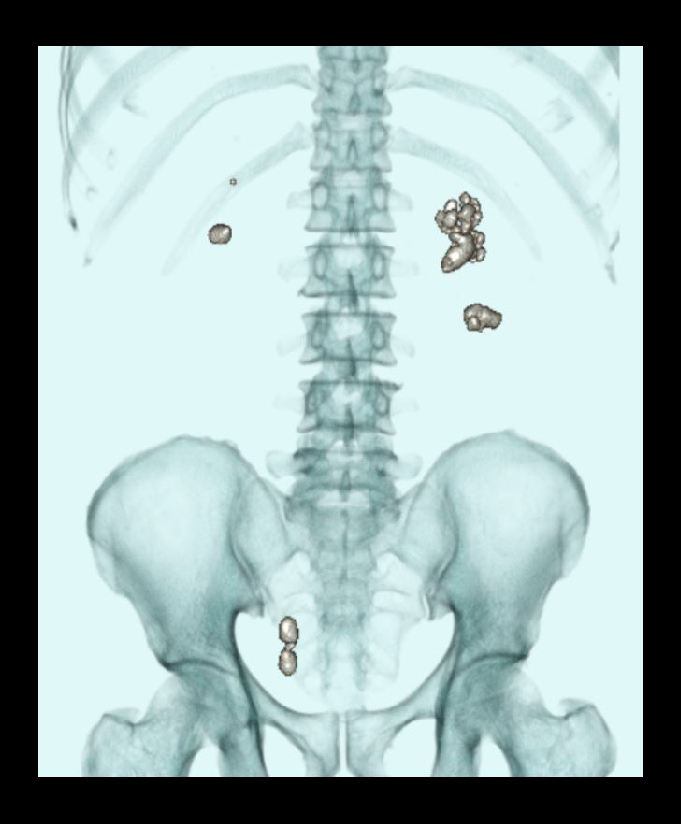

- Layered 3D images to show stones with respect to the lumbar spine.

- Measurements in length and width of each calculus.

- Measurement in Hounsfield unit (HU) of each calculus.